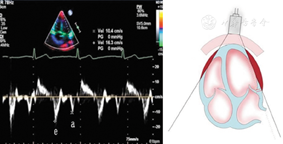

图18

标准心尖四腔切面引导脉冲波组织多普勒取样三尖瓣侧壁瓣环舒张期组织运动速度峰值e峰和a峰测量方法